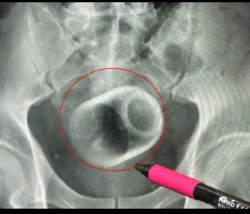

台中の男性は3日間排尿できなかった!なんと、肛門に「直径8cmの陶器カップ」が挿入されていたことが判明し、開腹手術で除去された。

「本当に信じられませんでした。見た時はショックでした」。手術後、外科医のウー・クンダ氏は患者に、どうやってカップが入ったのか尋ねた。患者は恥ずかしそうに「わかりません。偶然入れてしまったんです!」と答えた。患者は当初、排便のようにカップを排出しようとしたが、カップがしっかりと詰まってしまった。少なくとも3日間は排便できず、助けを求めて病院に駆け込んだ。

記事読むとアナル湯呑マンは人工肛門になったみたい